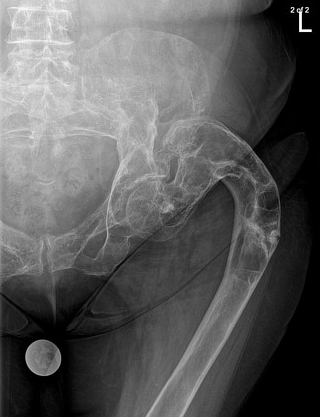

The HIP Greater Trochanter

Remember this is an epiphyseal equivalent and the chrondroblastomas prefer it to the femoral epiphysis. Plus, you can have avulsions of the gluteus medius and minimus.

The HIP Lesser Trochanter

An avulsion here without significant clinical history should make you think pathologic fracture.

The HIP The Intertrochanteric Region

Classic DDx here: Lipoma, Solitary Bone Cyst, Monostotic Fibrous Dysplasia, Liposclerosing Myxofibroma.